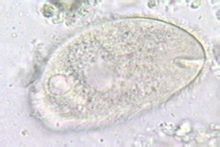

結腸小袋纖毛蟲生活史中有滋養體和包囊兩個時期。滋養體呈橢圓形,無色透明或淡灰略帶綠色,大小為30~200×25~120μm。全身披有纖毛,活的滋養體可借纖毛的擺動呈迅速鏇轉式運動。蟲體極易變形,前端有一凹陷的胞口,下接漏斗狀胞咽,顆粒食物借胞口纖毛的運動進入蟲體,形成食物泡經消化後,殘渣經胞肛排出體外。屬纖毛蟲門、少膜綱、腹口亞綱、盾纖目。蟲體略成葵花籽形,長50-75чm,寬20-50чm,內質不透明,蟲體中、後部各有一伸縮泡(contractilevacuo1e)具有調節滲透壓的功能。蘇木素染色後可見一個腎形的大核和一個圓形的小核,後者位於前者的凹陷處。包囊圓形或橢圓形,直徑為40~60μm,淡黃或淡綠色,囊壁厚而透明,染色後可見胞核。